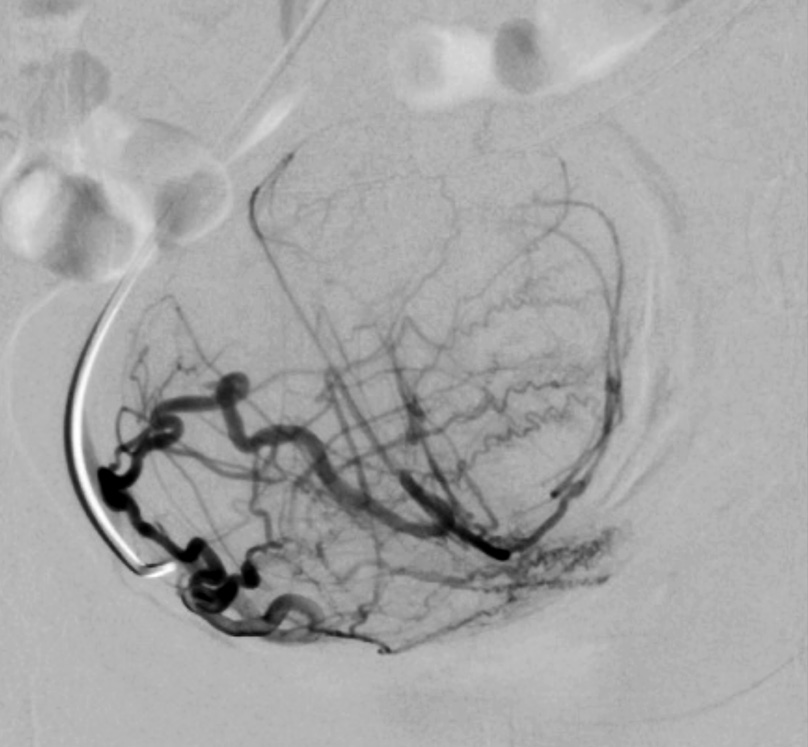

Выполнены пункция и катетеризация правой лучевой артерии в ретроградном направлении. Далее катетером выполнена селективная катетеризация правой и левой маточных артерий. Выявлена миома матки больших размеров с выраженным перифиброидным сплетением. При проведении ангиографии брюшной аорты и таза дополнительных источников кровоснабжения не выявлено. Катетер по проводнику проведен последовательно в горизонтальные сегменты левой и правой маточных артерий, питающих узлы (рис. 8, 9). Проведена эмболизация насыщенными гадотеридолом микросферами до стаза контраста в дистальных сегментах маточных артерий. Рентгеновский контроль эффективности эмболизации – рис. 10, 11. Катетер и интродьюсер удалены. Наложена давящая асептическая повязка.

Рис. 10. Клинический пример №2. Ангиограмма правой маточной артерии после ЭМА. / Fig. 10. Clinical case 2. Angiogram of the right uterine artery after UAE.

Рис. 11. Клинический пример №2. Ангиограмма левой маточной артерии после ЭМА. / Fig. 11. Clinical case 2. Angiogram of the left uterine artery after UAE.